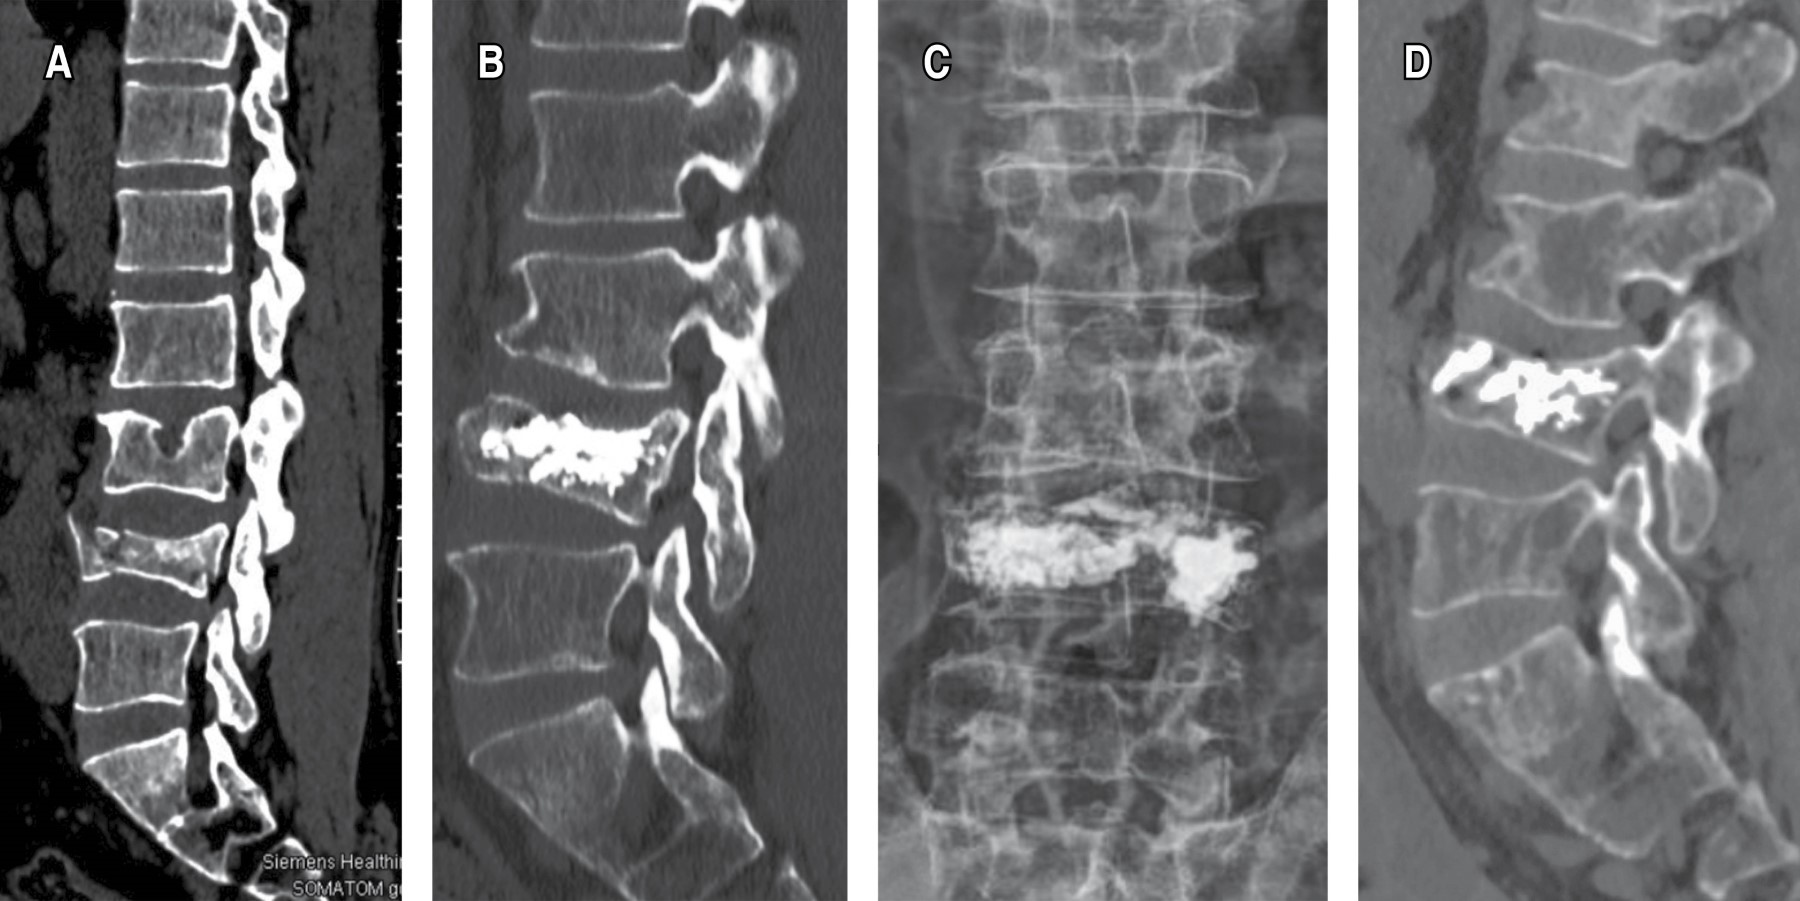

El presente estudio empleó un diseño ambispectivo, con una fase retrospectiva (enero de 2014 a diciembre de 2020) y una fase prospectiva (enero de 2021 a diciembre de 2024), siendo llevado a cabo en múltiples centros (Tabla 1). Se incluyeron pacientes, diagnosticados con fracturas vertebrales por compresión de uno a tres niveles mediante radiografías simples, tomografía de columna vertebral y resonancia magnética; pacientes que fueron intervenidos mediante cifoplastía combinada con radiofrecuencia pulsada (RF-P) en facetas articulares; pacientes con diagnóstico mediante densitometría de osteoporosis. Se excluyeron aquellos con infecciones activas en sitio de punción, trastornos hematológicos graves o casos con lesión medular con manifestación de síntomas y signos neurológicos.

El procedimiento quirúrgico se estandarizó para todos los participantes. La cifoplastía se realizó con el paciente bajo anestesia general o sedación profunda según el criterio anestésico individualizado. La técnica implicó la inserción percutánea de cánulas a través de abordaje posterior bilateral hasta alcanzar la vértebra afectada, seguida de inflado de balones específicos para la restauración de la altura vertebral y estabilización del cuerpo vertebral con cemento radiopaco (polimetilmetacrilato, PMMA). Posteriormente, de manera inmediata tras concluir la cifoplastía, se aplicó la técnica de RF-P en las facetas articulares correspondientes al nivel tratado. Este procedimiento fue realizado utilizando un equipo especializado de RF-P, ajustado a parámetros estandarizados (temperatura máxima de 42 °C, pulsos con duración de 20 ms y una pausa de 480 ms durante cuatro minutos por cada faceta articular tratada) (Figuras 1 y 2).